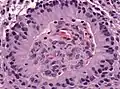

Периваскулярные псевдорозетки в эпиндимоме

Эпендимальные псевдорозетки вокруг пролиферирующего эндотелия при анапластической эпендимоме

Периваскулярные псевдорозетки состоят из спицевидных структур с конусообразными клеточными отростками, расходящимися вокруг стенки расположенного в центре сосуда. Приставка «псевдо» показывает различие этих розеток от розеток Гомера Райта и Флекснера-Винтерстайнера, потому что центральная структура розетки фактически не формируется самой опухолью, а вместо этого представляет собой нативную, неопухолевую ткань. Кроме того, некоторые ранние исследователи спорили о природе центрального просвета, выбирали приставку «псевдо», чтобы указать, что центр не является истинным просветом, а содержит гистологические структуры.[2]

Периваскулярные псевдорозетки встречаются в большинстве эпендимом независимо от степени злокачественности или варианта. Они значительно более важны для диагностики эпендимомы, чем истинные эпендимальные розетки. Но к сожалению, периваскулярные псевдорозетки менее специфичны — они также встречаются в медуллобластомах, PNET, центральных нейроцитомах и, реже, в глиобластомах, а также в редких детских опухолях, мономорфных пиломиксоидных астроцитомах.[2]